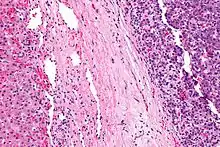

| Micrograph of a hepatoblastoma. H&E stain. | |